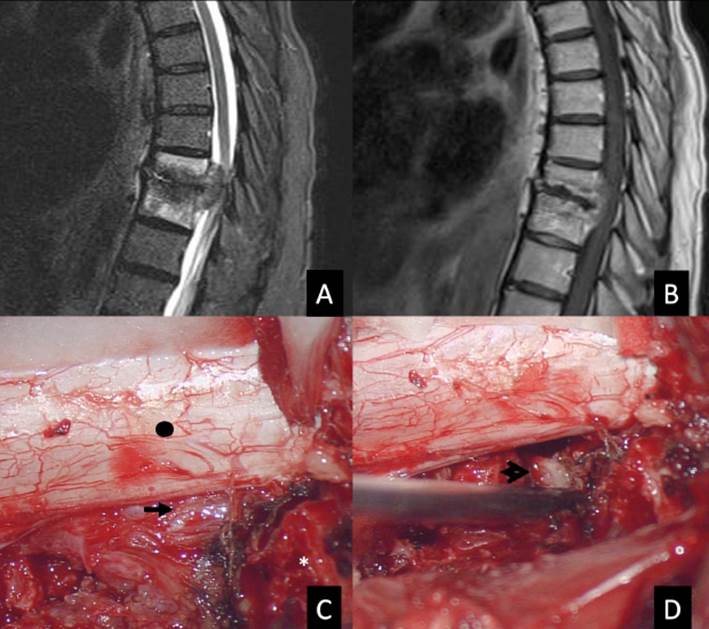

La RM puede detectar cambios tempranos y nos da información sobre la afectación de tejidos blandos, diseminación del absceso y la compresión de elementos neurales; además, con la administración de gadolinio ayuda a diferenciar la espondilodiscitis tuberculosa de otras causas bacterianas 10. Es necesaria la imagen de toda la columna, ya que pueden presentar lesiones "en salto" en el 2 a 16 %, y alcanzar, incluso, el 71 %, según un estudio 31. Las imágenes características en la RM son diseminación subligamentaria (84,8 %), colapso vertebral mayor de 50 % (69,6 %) y una gran colección de abscesos con pared delgada pre y paravertebral con extensión subligamentaria (91,1 %); el 97,5 % de los pacientes con TBE tienen al menos una de estas tres características en la RM, y el 58,2 %, las tres juntas 32 (Figura 1). También se describe señal baja en las imágenes ponderadas en T1 y señal brillante en las imágenes ponderadas en T2 de los cuerpos vertebrales afectados, la preservación relativa del disco y erosiones en las placas terminales 33. Cabe señalar que Chen et al. 10 encontraron que la tasa de afectación del disco es del 38 %, lo que puede estar en conflicto con nuestro conocimiento previo de que Mycobacterium tuberculosis no puede causar destrucción del disco en comparación con la infección espinal piógena; sin embargo, no es infrecuente encontrarlo en fases de destrucción avanzada. La sensibilidad y especificidad de la RM para el diagnóstico es de 100 % y 88,2 %, respectivamente 2,19.

Figura 1 Mujer de 27 años, con afectación vertebral D8, D9, D10 y D11, en etapa IV de destrucción vertebral, déficit neurológico Kumar 3 (con paraparesia 2/5 sin compromiso de esfínteres). A: RM parasagital derecha en T2 muestra destrucción y colapso de vértebra D9 y D10, compromiso discal, lesiones heterogéneas intraóseas y gran masa subligamentaria anterior. B: RM sagital en T2 que muestra la invasión intracanal con compresión medular, lo que ocasiona hiperintensidad intramedular. C: RM sagital en T1 con gadolinio que muestra la captación de contraste periférico: se evidencia una membrana delgada y bien definida de la lesión prevertebral e intracanal. D: RM axial en T2 a nivel de D9 que muestra la médula desplazada hacia la zona posterior y a la izquierda debido a la lesión intracanal. E: Radiografía de control luego del tratamiento con QTAT y cirugía de abordaje posterolateral (desbridamiento, corpectomía D9 y D10, colocación de canastilla de titanio y atrodesis transpedicular de D7 a L1).